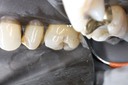

Scott Kanamori #31 pre-op

Scott Kanamori #31 amalgam removal